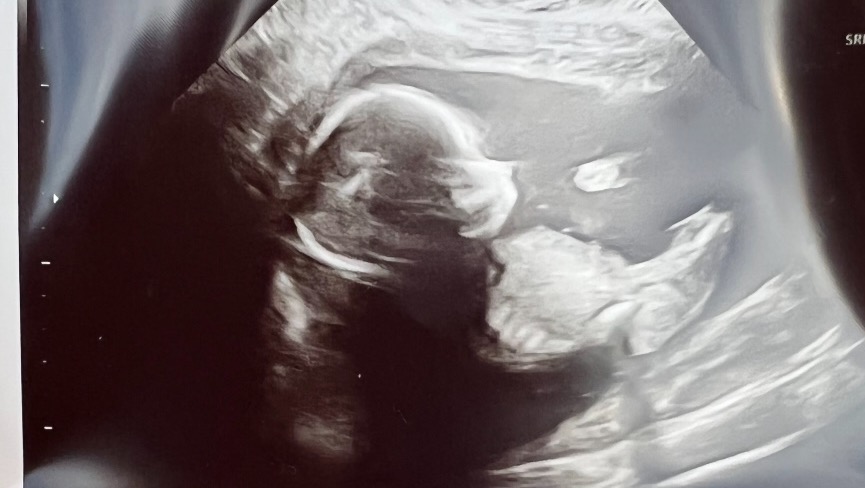

My baby sister, Emily and husband, Cody Pettis, are expecting their second baby girl, Emma Kate, due in July.

Their sweet girl has been diagnosed with Hypoplastic Right Heart Syndrome (HRHS) and will require several heart surgeries, the first being immediately after she is born. Her most recent appointment with the Neonatal Cardiac Surgeon has shown even further complications potentially requiring a heart transplant.